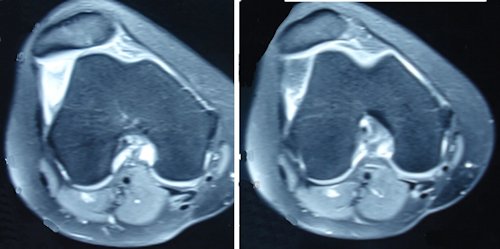

MRG'de transvers kesitler medial patello-femoral ligament hasarının yeri ve patellar dizilimin durumu hakkında önemli bilgiler verir. (Resim 1) Patella hala sublukse ise, troklear displazi ve patella alta varsa, tekrar çıkık olma riski çok yüksektir. Bu hastalarda osteokondral kırık olmasa bile ilk çıkıktan sonra cerrahi tedavi uygulanabilir. MPFL lezyonu patellaya yakın ise artroskopik teknikler uygulanabilir. MPFL lezyonu bağın gövdesinden veya femoral insersiyonundan ise açık teknikler gereklidir.

Troklear displazi'nin varlığı transvers MRG veya BT kesitlerinde değerlendirilir. Normalde vadi şeklinde olması gereken troklea, displazi varlığında giderek sığlaşır hatta konveks hale gelir. Bu durumda patellanın kemik stabilitesi kaybolarak instabilite riski artar. Dejour troklear displaziyi A'dan başlayıp şiddeti giderek artarak D'ye kadar 4 gruba ayırmıştır. A-C arası displazilerde genellikle MPFL veya tibial tüberküle yönelik girişimler yeterlidir. Tip D displazide, bu girişimlerle yeterli stabilite sağlanamıyorsa trokleoplasti gibi troklea derinliğini değiştiren girişimler gündeme gelmelidir.